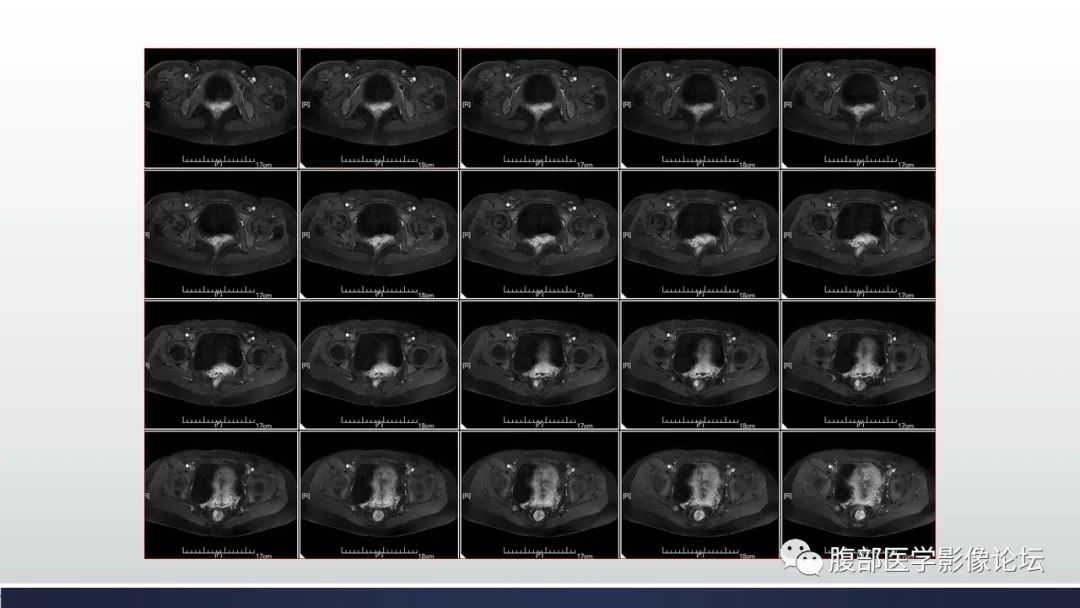

【病例】子宫内膜透明细胞癌1例MR-1

【病例】子宫内膜透明细胞癌1例MR-2

【病例】子宫内膜透明细胞癌1例MR-3

【病例】子宫内膜透明细胞癌1例MR-4